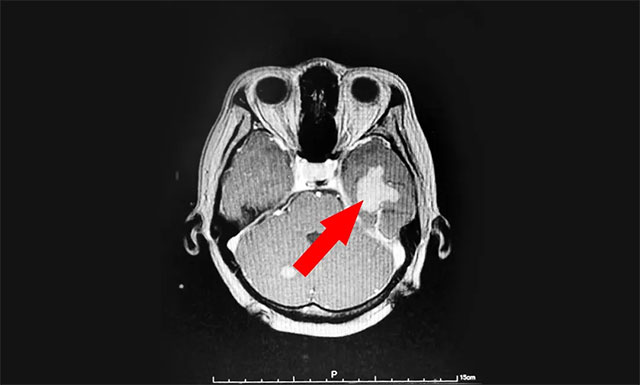

今年43岁的患者汤女士(化名),于2020年8月因头晕伴体倦乏力至当地医院就诊,查体PET-CT:右肺上叶前段结节,考虑周围型肺癌。右肺门、纵膈多发淋巴结转移,颅内多发转移。汤女士在外院接受放射治疗后,头晕乏力等症状得到了一定的改善。

▲ 来蓝十字治疗前患者的囊性转移瘤病灶